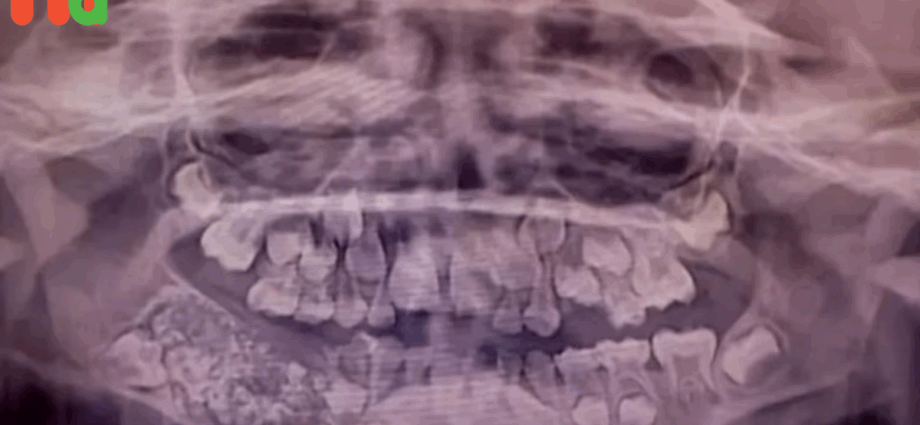

Las radiografías y tomografías computerizadas revelaron la presencia de una masa de aproximadamente 200 gramos alojada en el interior de la mandíbula. El Dr. Senthilnathan, responsable del Departamento de Cirugía Oral y Maxilofacial, identificó la anomalía como un “odontoma compuesto”, una variante benigna de tumor directamente relacionada con el desarrollo dental.

“La especie de tumor que detectamos impidió el crecimiento permanente de los molares en el niño en el lado afectado”, explicó el cirujano tras completar la operación. Las imágenes médicas mostraban numerosos dientes rudimentarios agrupados en un tejido con forma de bolsa, una presentación clínica poco frecuente en la literatura especializada.

La magnitud del descubrimiento sorprendió incluso a los médicos más experimentados. Según informó Science Alert, la bolsa contenía 526 pequeños dientes de dimensiones variables, desde apenas 0,1 milímetros hasta 15 milímetros de longitud. El proceso de clasificación y contabilización de cada pieza dental requirió cinco horas adicionales de trabajo meticuloso en el laboratorio.

La Dra. Pratibha Ramani, directora del Departamento de Patología Oral y Maxilofacial, destacó que todos los dientes extraídos presentaban las estructuras características de las piezas dentales normales: corona, raíz y recubrimiento de esmalte. “Incluso la pieza más pequeña tenía las características de un diente tradicional”, subrayó la especialista, quien enfatizó la ausencia de precedentes con tal número de dientes en los registros médicos mundiales.